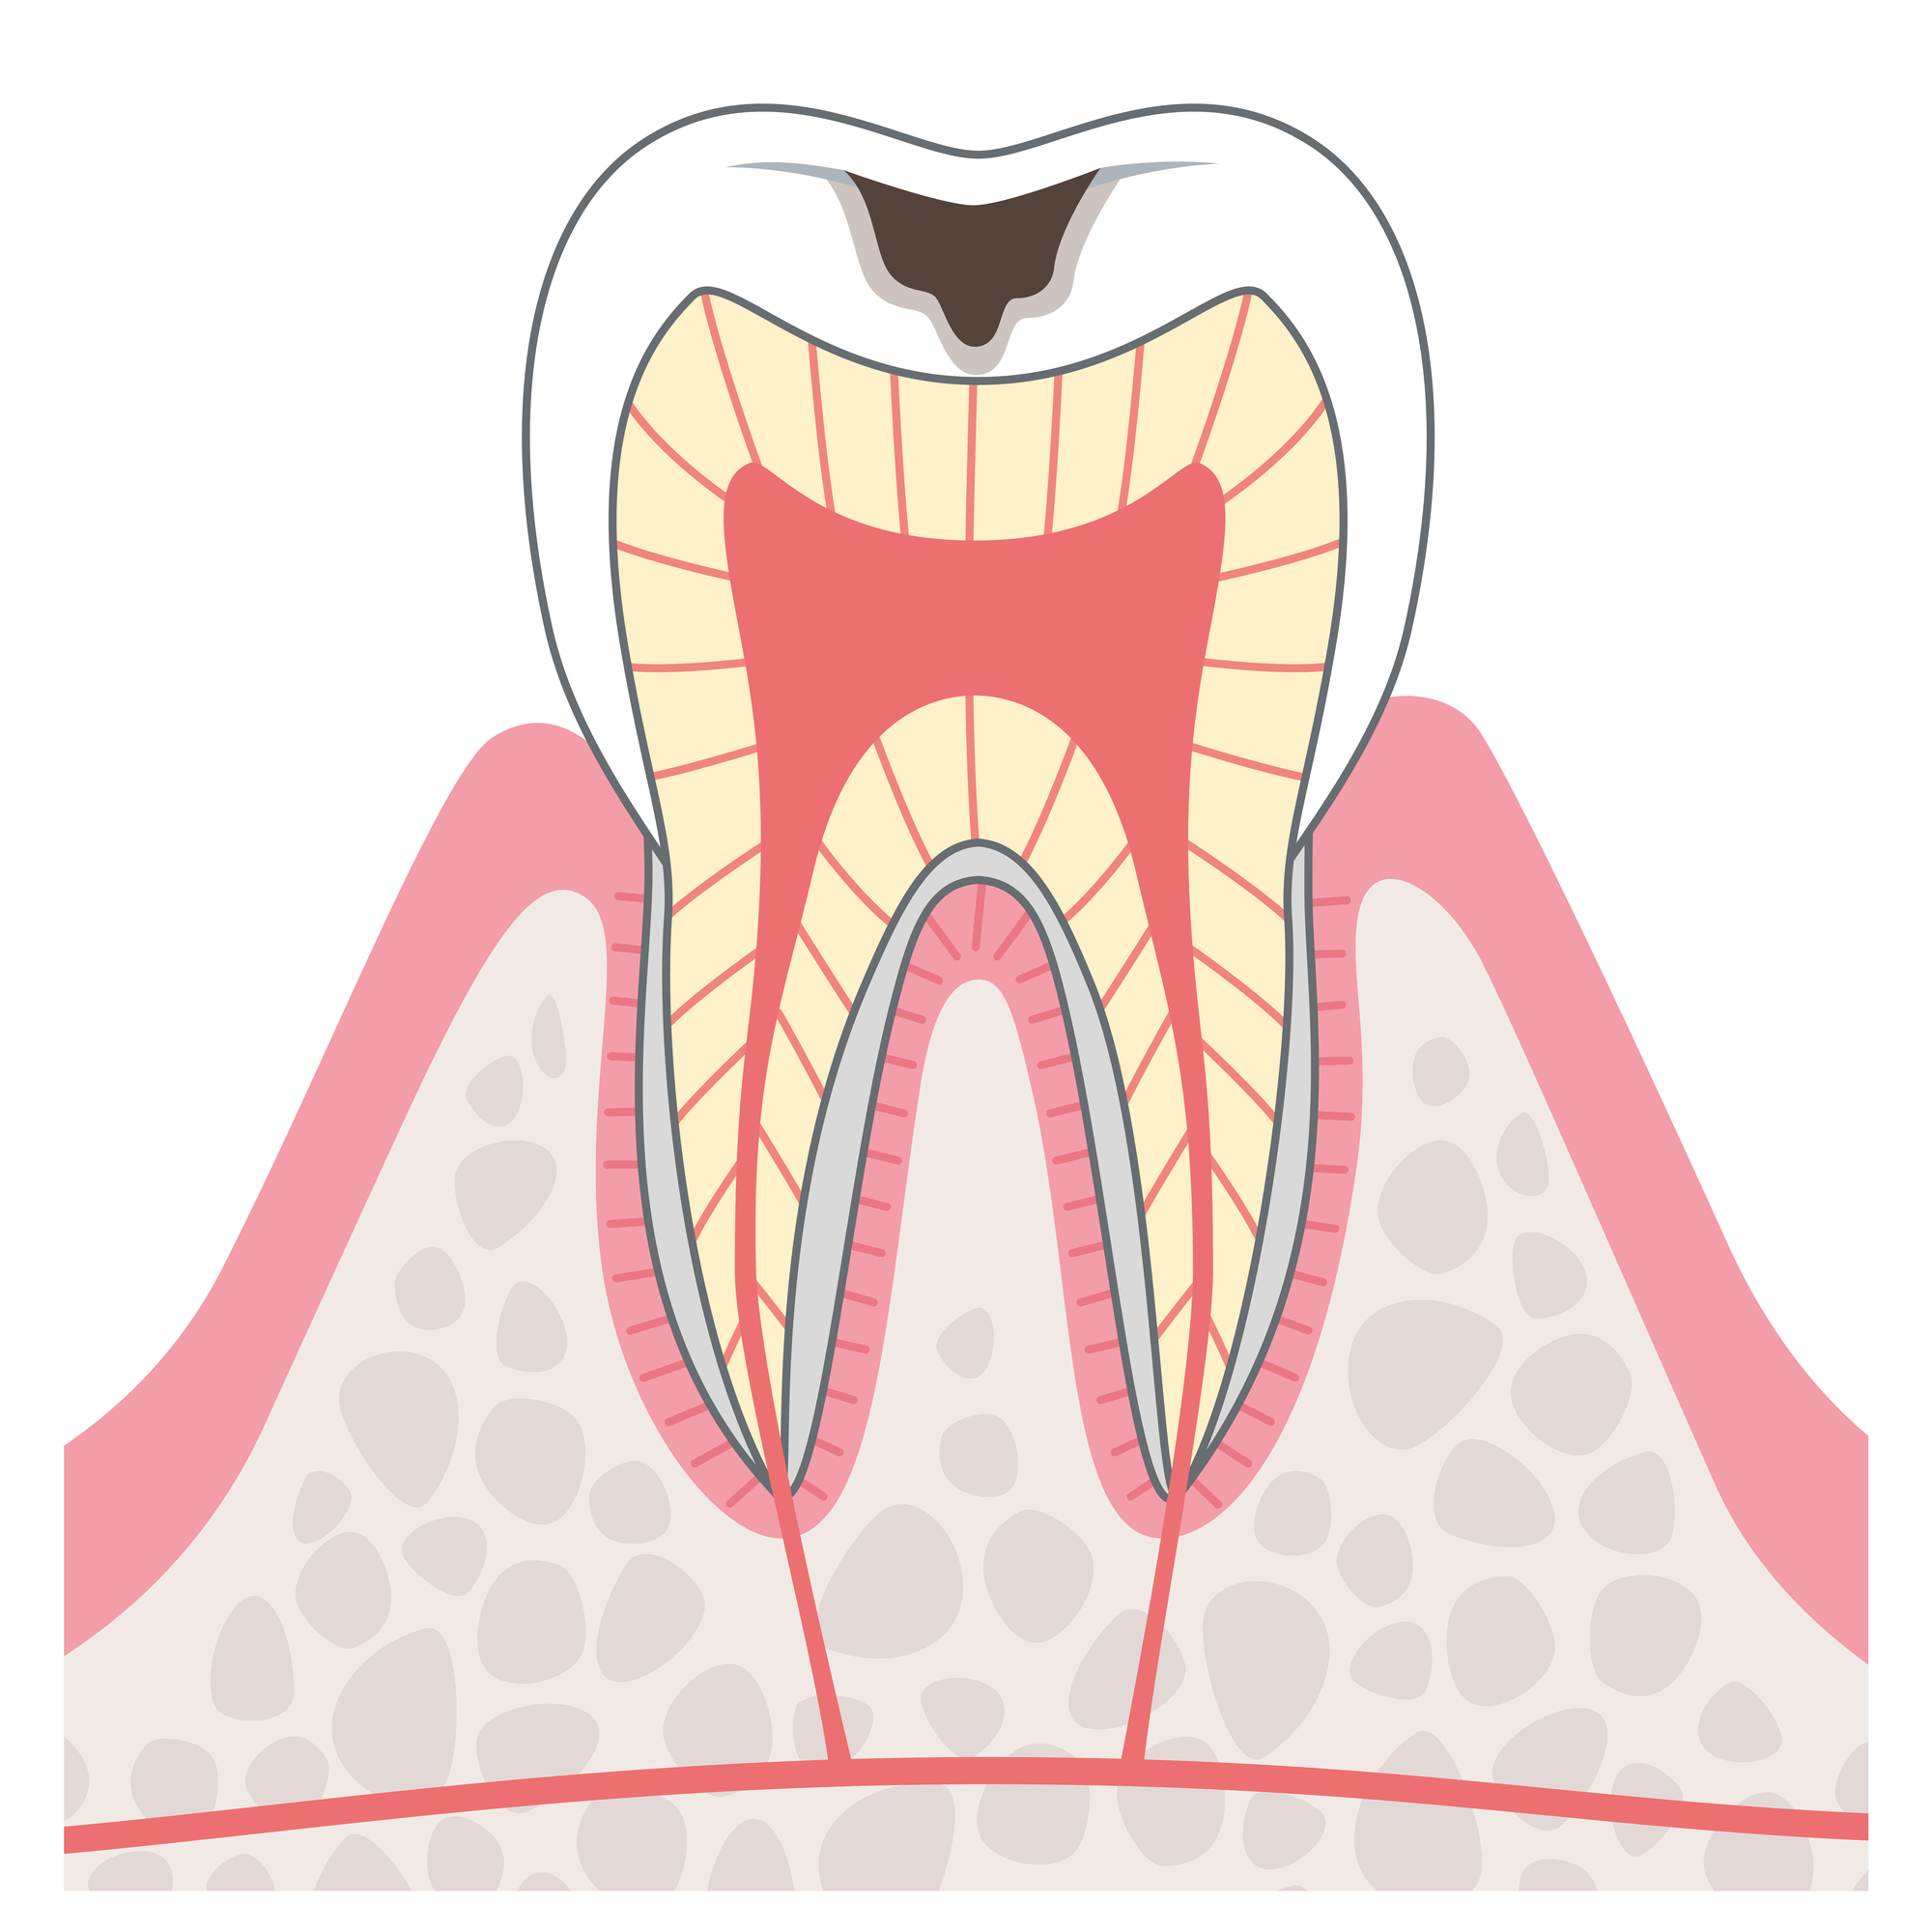

C2

この段階のむし歯は自然に治ることはないため、放置せずお早めの受診がおすすめです。

治療方法

- 詰め物